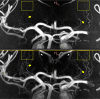

7 Tesla-field-strength (7 T) Magnetic Resonance Imaging allows the small perforating arteries in the brain to be visualised, and this modality may allow visualisation of the arterial pathology in cerebral small vessel disease. Most studies have used standard Time-of-Flight (ToF) Magnetic Resonance Angiography (MRA). Whether the use of contrast enhancement improves perforating artery visualisation at 7 T remains unclear. In a prospective study, we compared standard ToF MRA with contrast-enhanced (CE) ToF MRA at 7 T for the visualisation of the lenticulostriate arteries (LSAs). Ten patients with symptomatic lacunar stroke were recruited (mean age, SD, 64 ± 9.9 years). Visualisation was assessed using a visual rating scale administered by two independent expert readers and length of the LSAs visible. Visualisation of the LSAs was improved with CE ToF MRA. The mean Visibility and Sharpness Score was higher for CE ToF MRA over standard ToF MRA (2.55 ± 0.64 vs. 1.75 ± 0.68; P = 0.0008). The mean length of LSA visualised was significantly longer with CE ToF MRA compared to standard ToF MRA (24.4 ± 4.5 vs. 21.9 ± 4.0 mm; P = 0.01). CE ToF MRA offers improved visualisation of the LSAs over standard ToF MRA. The addition of contrast may improve the ability to visualise cerebral small vessel disease arterial pathology.